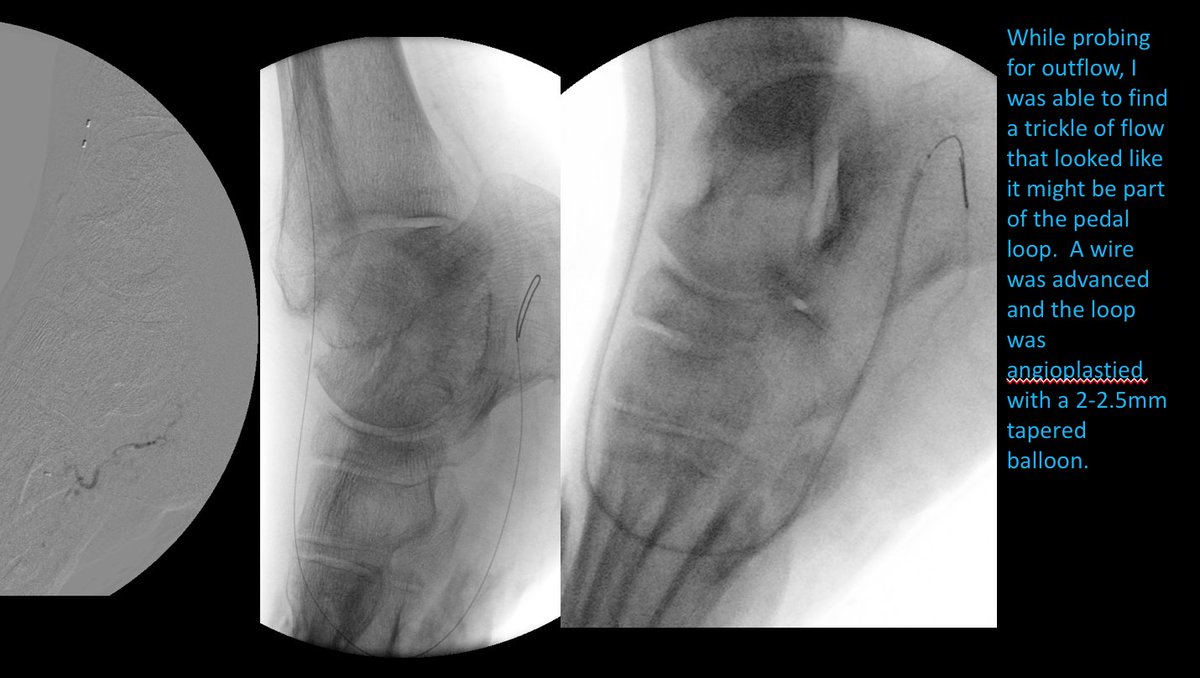

82 yo F with R5 ulcers of 3rd & 4th toes. #IRad can help with infrapopliteal and pedal revascularization to #StopTheChop. #mylegmylife #CLIFighters @SIRspecialists @SIRRFS @CLI_Global @AMPSymposium @pj_rochon

AlexCVIR's tweet image. 82 yo F with R5 ulcers of 3rd & 4th toes. #IRad can help with infrapopliteal and pedal revascularization to #StopTheChop. #mylegmylife #CLIFighters @SIRspecialists @SIRRFS @CLI_Global @AMPSymposium @pj_rochon